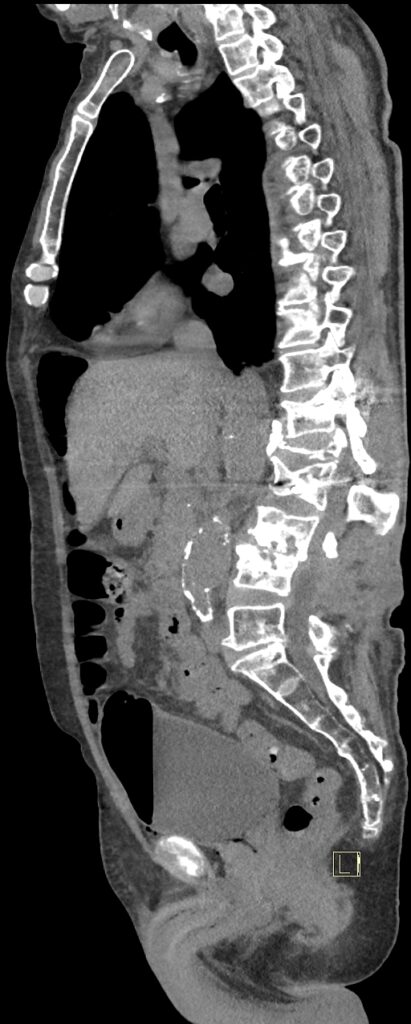

CAZ nr 131: Cistită emfizematoasă

Figurile 3 şi 4: sagital examinare CT abdomen şi pelvis fără substanță de contrast

Discuţie caz nr 131: pacient de 85 de ani cunoscut diabetic este adus la camera de gardă pentru dureri abdominale difuze, efectueaza CT fără substanță de contrast deoarece eGFR este 21 mL/min/1.73 m². Se evidențiază pericardita în cantitate medie, mai multe chiste renale – unul spontan hiperdens, multiple plăci aterotrombotice calcificate la nivelul aortei și ramurilor precum și multiple bule aerice în peretele vezicii urinare și conținut hidro-aeric al vezicii urinare. Ultimele două elemente sugerează diagnosticul de cistita emfizematoasă.

DE LUAT ACASĂ!!! Cistita emfizematoasă este o infecție gravă, dar rară, a vezicii urinare, în care bacteriile producătoare de gaze creează bule de aer în peretele vezicii urinare, adesea asociate cu diabetul necontrolat, mai rar cu utilizarea cateterului sau vezica urinară neurogenă. Simptomele includ dureri abdominale inferioare, febră și urinare dureroasă sau frecventă, dar diagnosticul necesită tomografie computerizată pentru a observa gazele. Tratamentul implică antibiotice și gestionarea afecțiunilor subiacente, fiind posibil necesară intervenția chirurgicală în cazurile severe, deși tratamentul prompt duce de obicei la un rezultat favorabil.